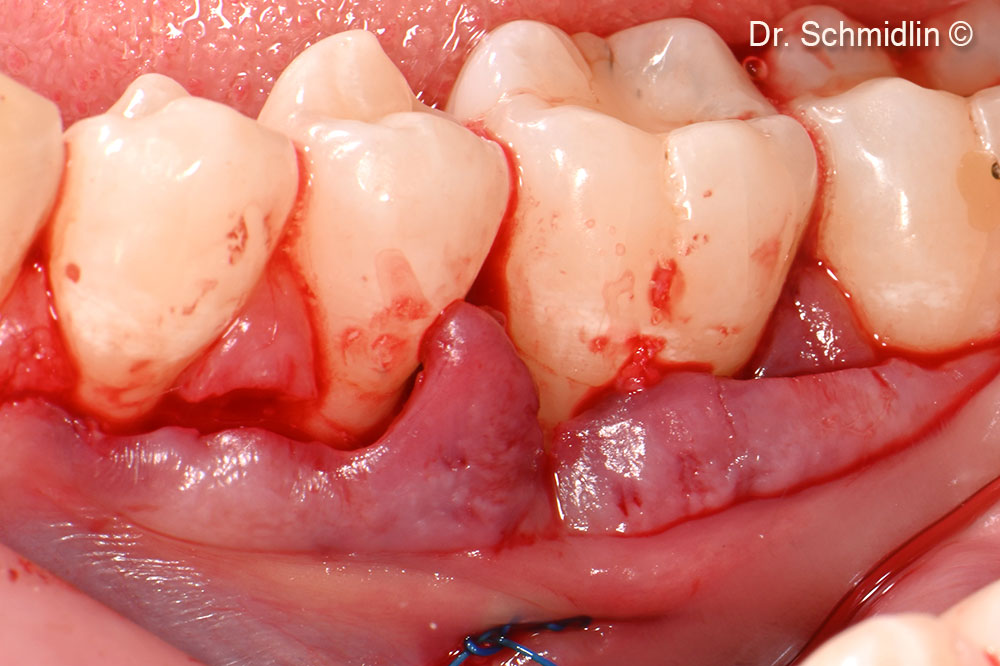

Preoperative clinical view of the affected site